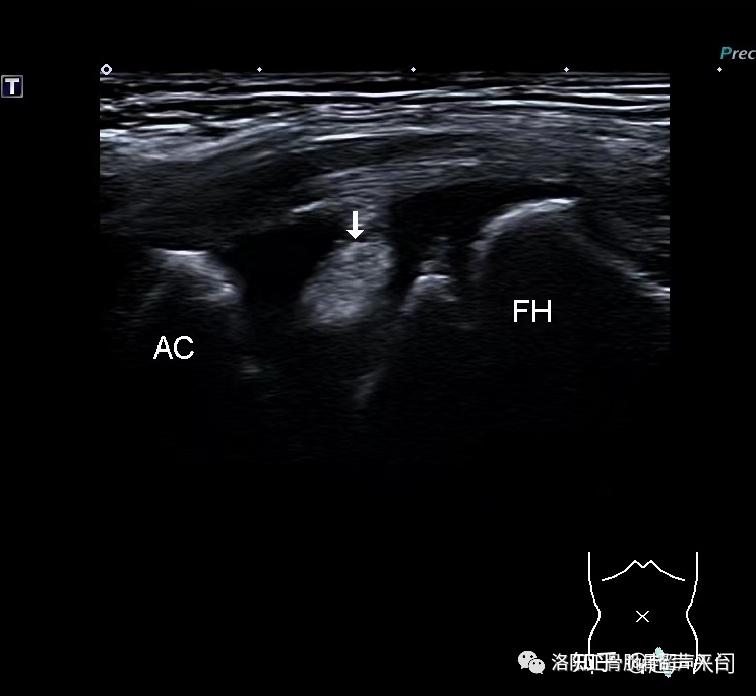

病例分享小儿髋关节滑膜嵌顿症

图片尺寸521x525

图片尺寸756x696